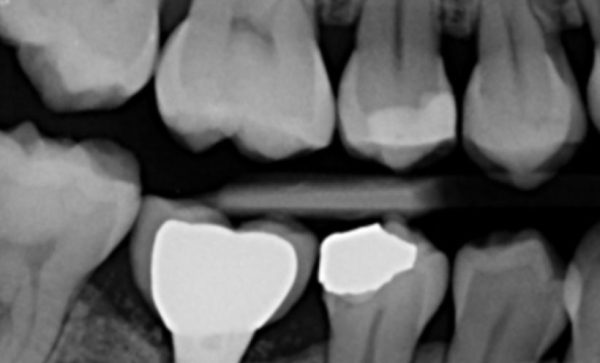

Case 46